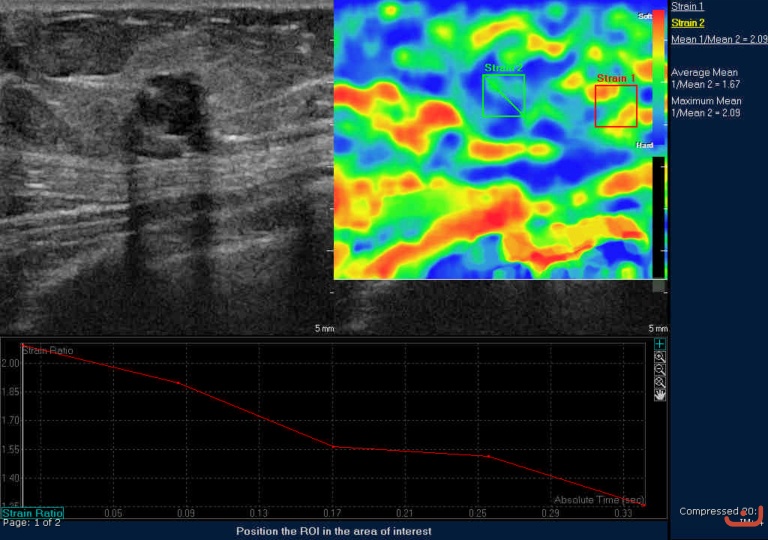

Case 42-E1

Malignant solid mass